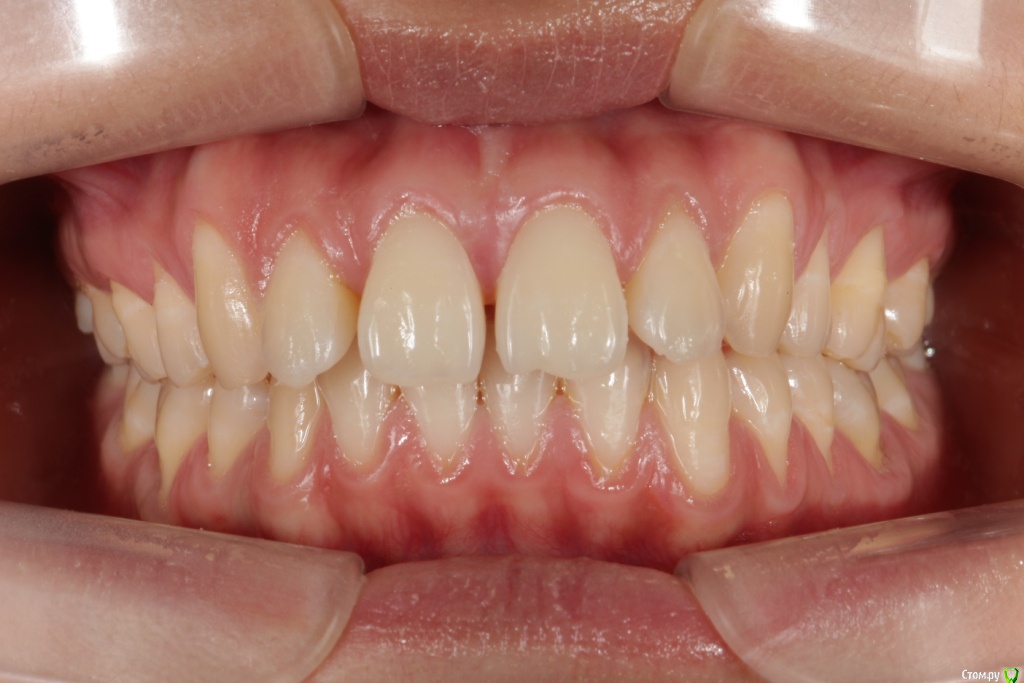

Головные боли, артроз ВНЧС, дистальный глубокий прикус, удалены 4ки на вч и 5 на нч

Сейчас мне 25 лет. С детства был дистальный глубокий прикус, зубы на верхней челюсти выпирали вперед, на нижней челюсти присутствовала скученность, из-за чего была удалена "мешающая" 5ка. Вероятно, этот зуб стоило сохранить.

В 2007-2008 гг. проходила ортодонтическое лечение с удалением 4ок на верхней челюсти. Резцовые зубы были перемещены назад, эстетически результат был удовлетворительным. Однако, проблема неправильного прикуса решена не была.

То, что эти боли могут быть следствием проблем с ВНЧС, узнала в последнюю очередь. МРТ показало, что у меня артроз суставов - 3 степени слева, полная вентрально-латерация дислокация суставного диска без репозиции; 1 степени справа, с репозицией, гипермобильность правого сустава. Асимметрии лица нет, однако рот открывается по S-образной траектории (почти не заметно), при широком открывании рта очень редко слышен щелчок, хрустов нет, слегка выпирает правый сустав. Заключение по МРТ с подробным описанием в приложении.

Была на консультации у ортопеда, который в качестве решения предложил выдвинуть нижнюю челюсть вперед с помощью ношения ортотика и брекет-системы. При этом перед началом и в ходе лечения указал на необходимость удаления 8ок (наверное, только на верхней челюсти) и "возвращения" 4ок за счет имплантов. Аргументировано это было тем, что премоляры играют важнейшую роль, в то время как 8ки вроде рудиментов; а ортодонтическое лечение с удалением 4ок устарело и в большинстве случаев не показано.

P.S: необходимо ли закрывать рецессии до начала лечения? или лучше сделать это после окончания лечения?

Заключение по МРТ, ОПТГ, цефалограмма в боковой проекции (справа и слева) и фото зубов - в приложении.